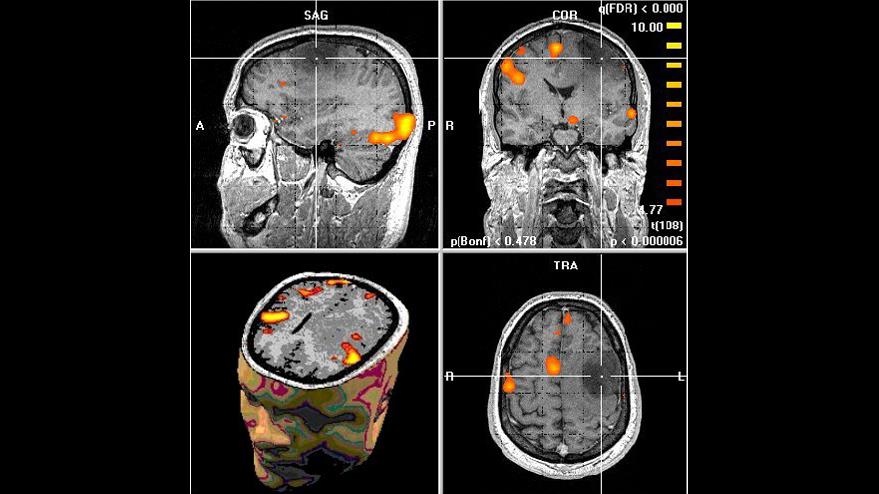

En el estudio, los investigadores utilizaron imágenes de una resonancia magnética funcional y otras técnicas para tener una visión detallada de la actividad cerebral en voluntarios.